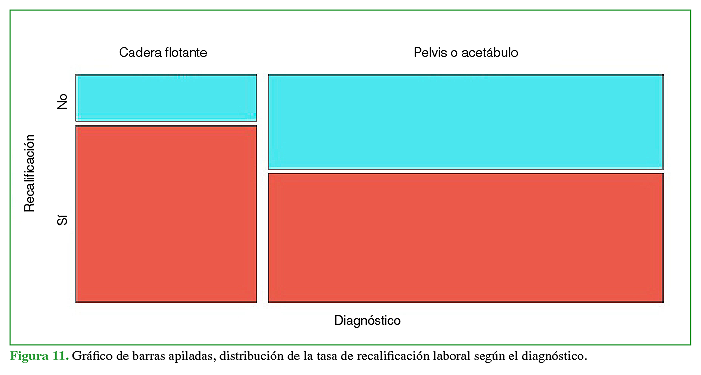

Las diferencias entre los grupos con respecto a la incapacidad laboral temporaria resultaron estadísticamente significativas (p = 0,00012). No hubo diferencias estadísticamente significativas en la tasa de recalificación laboral, entre los grupos en función del diagnóstico de CF (p = 0,11) (Figuras 10y 11).

Al analizar la tasa de recalificación laboral no se encontraron diferencias estadísticamente significativas. La tasa de recalificación puede estar relacionada con la actividad laboral de cada paciente y las lesiones asociadas no ortopédicas que no fueron evaluadas en este estudio. Tampoco encontramos bibliografía al respecto.

En nuestra serie, los pacientes con CF requirieron más procedimientos quirúrgicos y días de internación, y la incapacidad laboral transitoria fue mayor, con el consecuente aumento de los días de rehabilitación, frente a las fracturas aisladas de pelvis o acetábulo; no se hallaron diferencias en la tasa de recalificación laboral.